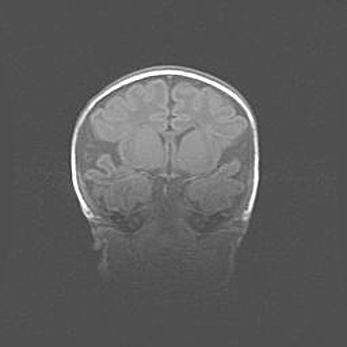

Открытая гидроцефалия.

Возраст: 9 месяцев 12 дней

Вес: 6800 г

Пол: мужской

Окружность головы: 41,5 см

Срок гестации: 28 недель

Гидроцефалия головного мозга у новорожденных имеет характерный признак: опережающий рост окружности головы приводит к визуально хорошо определяемой гидроцефальной форме сильно увеличенного в объёме черепа. Детские неврологи определяют следующие симптомы гидроцефалии у грудничков: выбухающий напряжённый родничок, частое запрокидывание головы, смещение глазных яблок к низу.